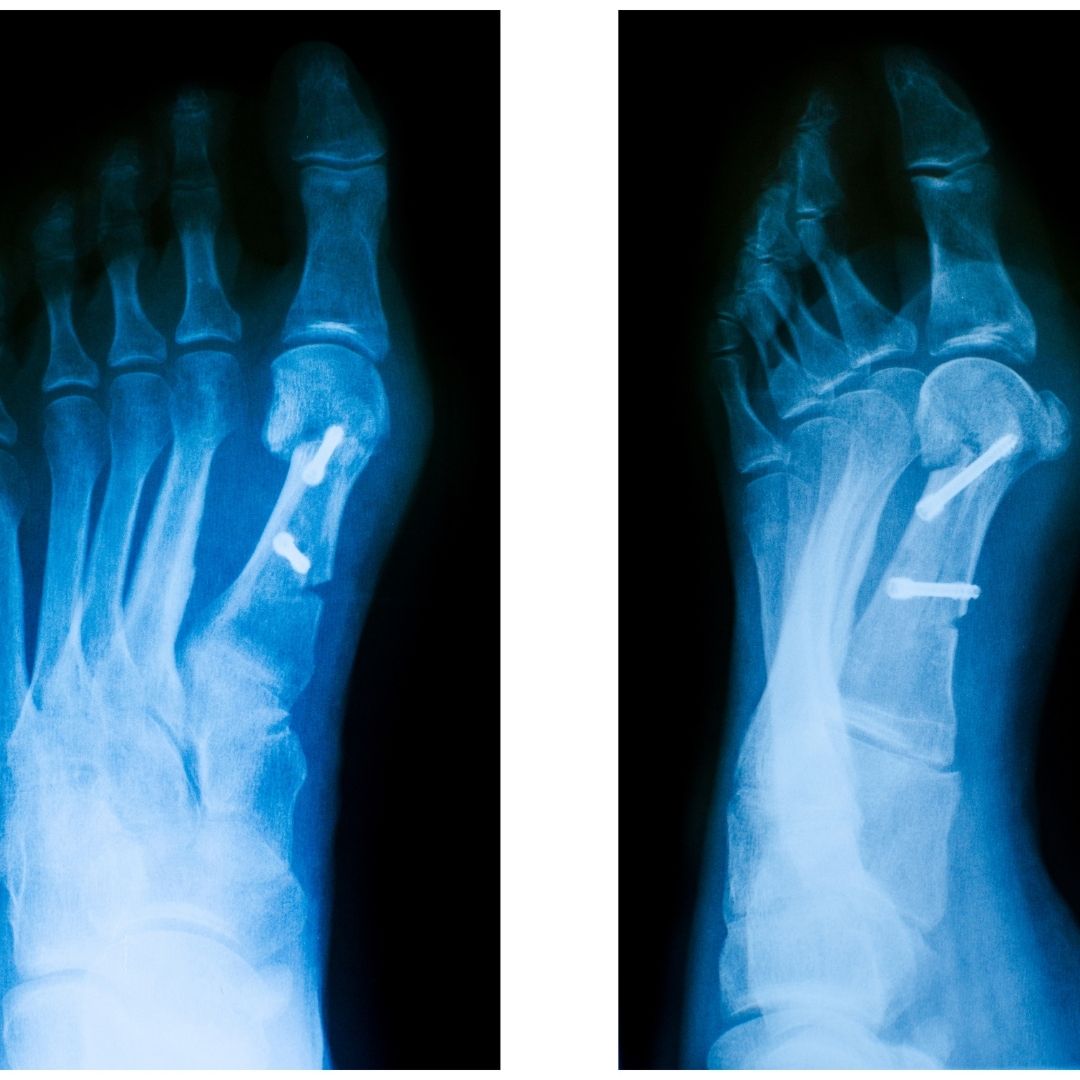

In the first stage of the disease, swelling appears as redness and pain. In the second and third stages, the complaint gradually increases. You see that the joint here deteriorates.

In the last stage, two fingers go on top of one finger, in other words, contrary to what is affected, it is said that the bone has protruded on the big toe, but in fact it is a protrusion of the bone itself. We classify it in four stages, the first stage is swelling and redness of the skin under the skin, the second stage is that it comes towards the inner part of the metacarpal bone, the third stage is that the nail part of one finger goes outwards, and in the fourth stage, the pain intensifies and one finger comes on top of two fingers.